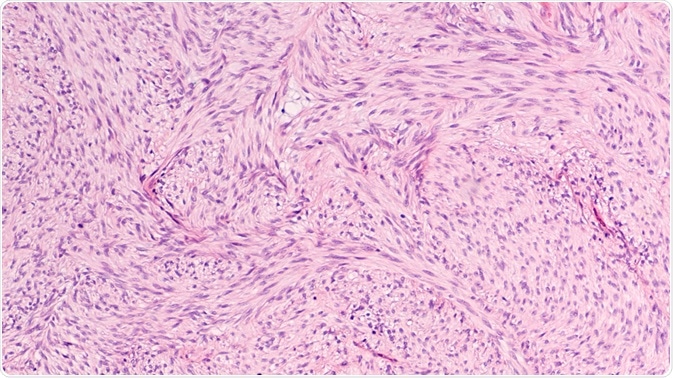

Stromal Tumor

Image Credit: David A. Litman/Shutterstock.com